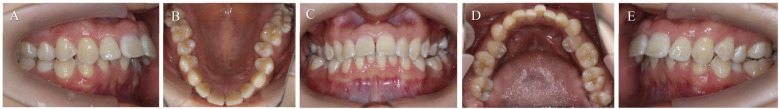

牙根吸收是正畸治疗后的主要并发症之一。这是一种涉及缺血性坏死的炎症过程。因此,它被称为正畸诱导炎症根吸收(OIIRR)。本报告的目的是提出一个病例研究的患者在她的20谁经历了内根吸收在两个上颌中门牙的正畸治疗的结果。将三氧化二矿聚集体(mta)应用于根吸收损伤以促进再矿化。经过3年的随访,临床和影像学检查显示未发现与吸收性病变相关的透光度,无任何病理症状。

Root resorption is one of the leading complications that follows orthodontic treatment. It's an inflammatory process involving ischemic necrosis. Therefore, it is called orthodontically induced inflammatory root resorption (OIIRR). The purpose of this report is to present a case study of a patient in her 20s who experienced internal root resorption on two maxillary central incisors as a result of orthodontic treatment. Mineral trioxide aggregates (MTAs) were applied to the root resorption lesion to promote remineralization. A clinical and radiographic examination revealed that no radiolucency related to the resorptive lesion was found without any pathological symptoms after a 3-year follow-up.